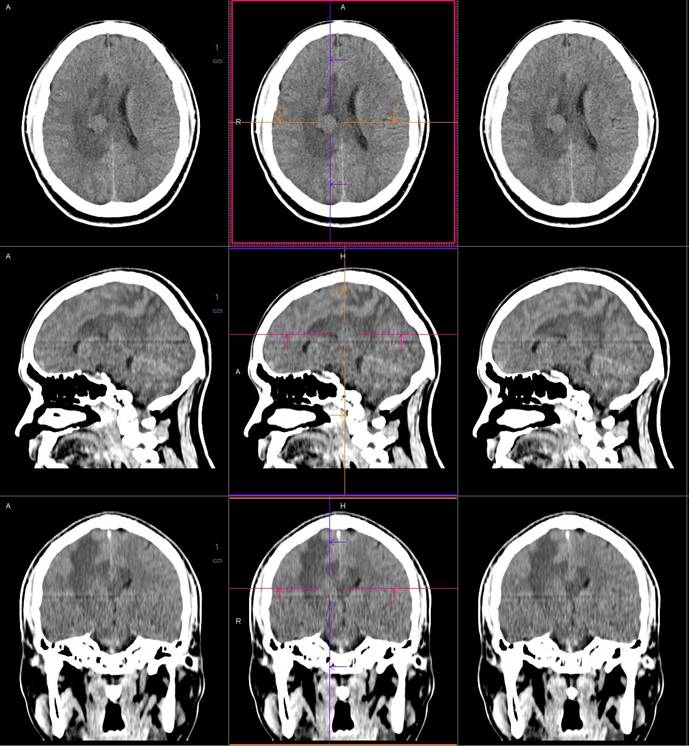

磁共振影像圖

圖1

圖2

圖3

圖4

MR診斷:右側(cè)側(cè)腦室三角區(qū)及側(cè)腦室旁占位,考慮惡性腫瘤可能,間變型腦膜瘤?轉(zhuǎn)移瘤?

CT是腦腫瘤的常用檢查方法,CT平掃及增強(qiáng)通過(guò)腫瘤的形態(tài)、密度及血供情況等對(duì)腦膜瘤的診斷和鑒別診斷有一定的價(jià)值。腦膜瘤為腦外腫瘤,但瘤周腦實(shí)質(zhì)水腫的出現(xiàn)率也較高,國(guó)外報(bào)道約60%。本例非典型腦膜瘤可見(jiàn)顯著的瘤周水腫。導(dǎo)致瘤周水腫的機(jī)制仍不明確,可能由多種因素參與、共同影響、相互制約所引起的一種血管源性水腫,腫瘤壓迫鄰近引流靜脈容易產(chǎn)生水腫,也有學(xué)者認(rèn)為與腫瘤的血管內(nèi)皮生長(zhǎng)因子、水通道蛋白-4高表達(dá)等因素有關(guān)。

MR鑒別診斷

常規(guī)MR檢查是診斷腦膜瘤的有效手段,可以明確腫瘤發(fā)生的部位、形態(tài)和數(shù)目等特征以及病變向鄰近腦實(shí)質(zhì)侵犯的程度和范圍,典型腦膜瘤呈等或(和)稍長(zhǎng)T1、等或(和)稍長(zhǎng)T2信號(hào),??娠@示完整的包膜,增強(qiáng)掃描因腫瘤內(nèi)部新生血管通透性不同呈不同程度強(qiáng)化,由于腫瘤組織的強(qiáng)化程度與腫瘤的惡性程度不完全一致,導(dǎo)致MR常規(guī)檢查在腦膜瘤分級(jí)分型方面仍存在一定的困難。擴(kuò)散加權(quán)成像( diffusion weighted imaging,DWI) 及表觀擴(kuò)散系數(shù)( apparent diffusion coefficient,ADC) 被廣泛用于腦腫瘤的分級(jí)、分子分型和腫瘤侵襲性預(yù)測(cè),并取得了良好的性能。目前,對(duì)于非典型腦膜瘤腦實(shí)質(zhì)侵犯的診斷的金標(biāo)準(zhǔn)依賴于組織病理學(xué)。